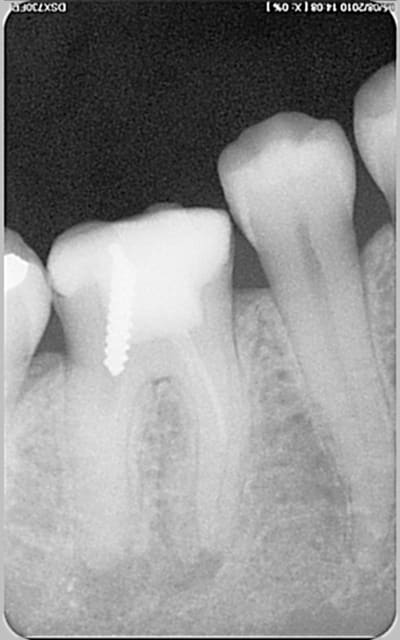

encore des radios,peut-etre assez moyen comme traitement...mais je vu pire...

les dernieres radios. patient en urgence ,abces... il voulait pas extraire la dent. j'ai lui bien explque et il a choisi de essayer de garder la dent. retrait,pas d'isolation avec la digue donc pas de tenon fibree,amalgam et screw post.traitement fait il ya 2 ans je crois.patient fidel de cabinet maintenent.